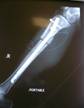

Unilateral tibia lengthening in 16year old girl using ISKD

Immediate Post Op

Lengthening proceeding well

Good regenerate formation with 5cm lengthening